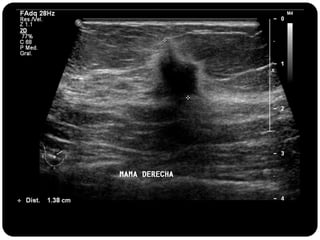

Paciente femenina de 66 años con historia clínica de 1er gesta antes de los 30 años y antecedentes de lactancia positiva, presenta una lesión palpable en la mama derecha. Los estudios radiológicos indican un diagnóstico de bi-rads 5, con biopsias revelando adenocarcinoma lobulillar infiltrante en la glándula mamaria derecha y adenocarcinoma ductal in situ en la izquierda. El caso fue evaluado por las doctoras Jacqueline Preciado Vargas y Beatriz E. González Ulloa.